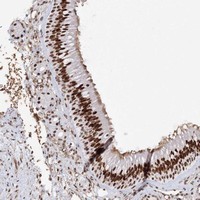

- Experimental details

- Immunohistochemical staining of human nasopharynx with ZNF638 polyclonal antibody (Cat # PAB23057) shows strong nuclear positivity in respiratory epithelial cells at 1:200-1:500 dilution.

- Validation comment

- Immunohistochemistry (Formalin/PFA-fixed paraffin-embedded sections)